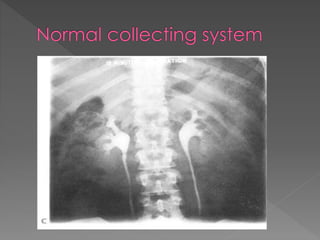

 Pyelogram:

 Excretion of contrast into the pelvis &

ureter